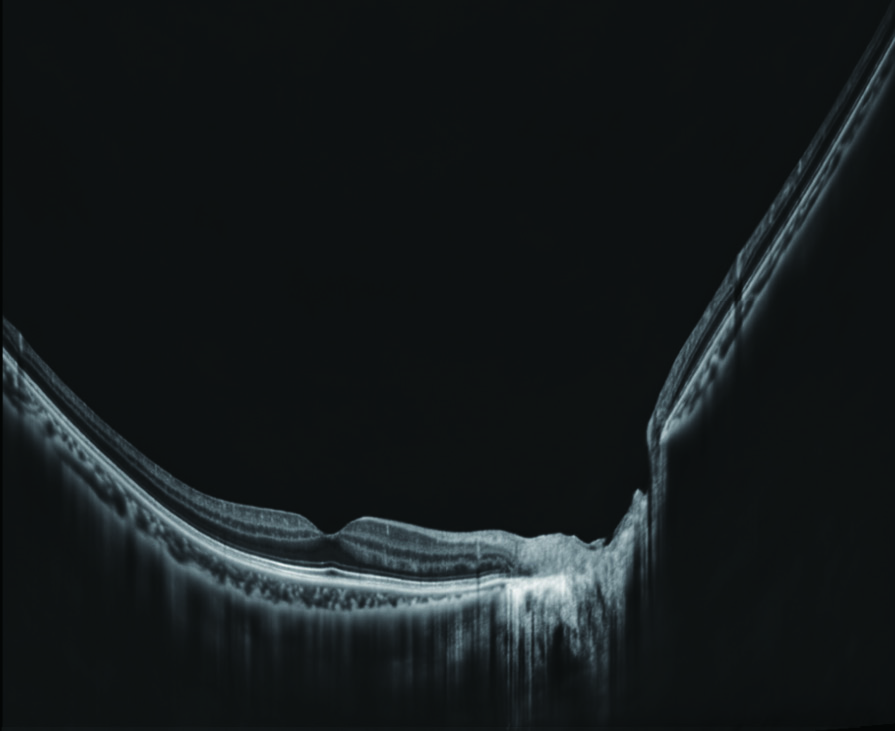

Macula line 16.5 mm - Scan depth 4.2 mm / OCT-Angiography 6 x 6, 9 x 9, 12 x 12 mm

Macula Radial 12 (15mm), Fine Choroidal